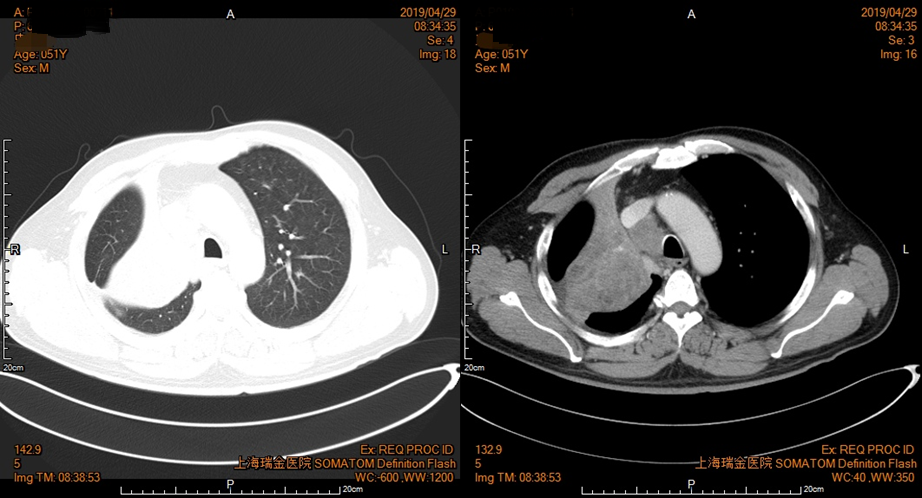

2019年4月29日复查胸部CT(图2),提示较2019年2月21日有所进展,完善气管镜,提示未见异形成分,评估为SD后继续治疗。

图2 患者胸部CT影像资料(2019年4月29日)